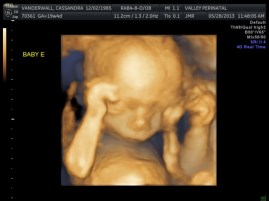

The biggest one in the bunch is Baby B at 2lbs and 12oz at the 62nd percentile. Little Elle Rose (Baby E) is the munchkin, but not by much as baby D and Theo (baby A) are also the same weight (2 ½ lbs) but just a bit longer. At this rate, when the baby’s are measured again at 32 weeks they will be about 1lb heavier each. Let’s just hope this Mama can keep up!